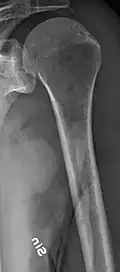

-

X-ray of the forearm, with lytic lesions -

Multiple myeloma in the upper arm -

Femur with multiple myeloma lesions -

Same femur before myeloma lesions for comparison -

The diagnostic examination of a person with suspected multiple myeloma typically includes a skeletal survey. This is a series of X-rays of the skull, axial skeleton, and proximal long bones. Myeloma activity sometimes appears as "lytic lesions" (with local disappearance of normal bone due to resorption) or as "punched-out lesions" on the skull X-ray ("raindrop skull"). Lesions may also be sclerotic, which is seen as radiodense.[76] Overall, the radiodensity of myeloma is between −30 and 120 Hounsfield units (HU).[77] Magnetic resonance imaging is more sensitive than simple X-rays in the detection of lytic lesions. An MRI may supersede a skeletal survey, especially when vertebral disease is suspected. Occasionally, a CT scan is performed to measure the size of soft-tissue plasmacytomas. Nuclear Medicine Bone scans are typically not of any additional value in the workup of people with myeloma (no new bone formation; lytic lesions not well visualized on nuclear bone scan).